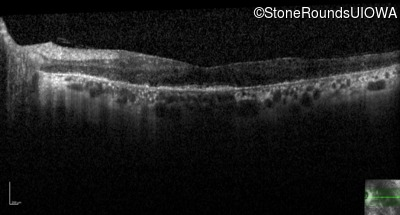

Optical Coherence Tomography - Right - 20/30

Exemplar / OCT Stack

OCT Stack

Optical Coherence Tomography - Left - 20/100